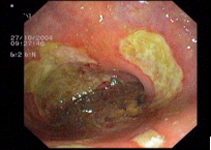

Endoscopic images:

imagen3

Multiple rectal ulcer